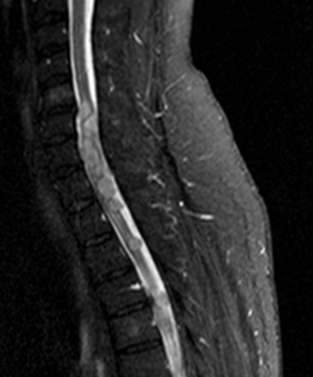

MRI: only MRI can provide a definitive diagnosis by depicting the expanded region within the axis of the spinal chord as an expansile lesion showing liquor intensity on all sequences (weak T1 signal and strong on T2 weighted imaging).

On MRI its characteristic loss of signal is accompanied by edema in the spinal chord (strong T2W signal).

Ependymomas rather occur in adulthood (they can also be the metastases of primary cerebral ependymomas) thoracic spinal chord, medullary cone, filum terminale.

MRI: On T1 withed images it shows isointense with the spinal chord, while on T2W images it is hyperintense.

Contrast enhancement is strong, it can be inhomogeneous.